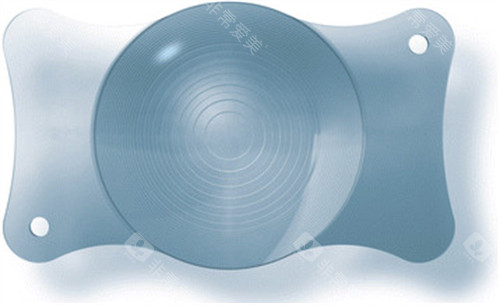

PRL晶体植入手术采用的是较高的技术和高品质的晶体材料。

这种晶体具有良好的生物相容性,能够与眼内组织协调共处,减少排异反应的发生。